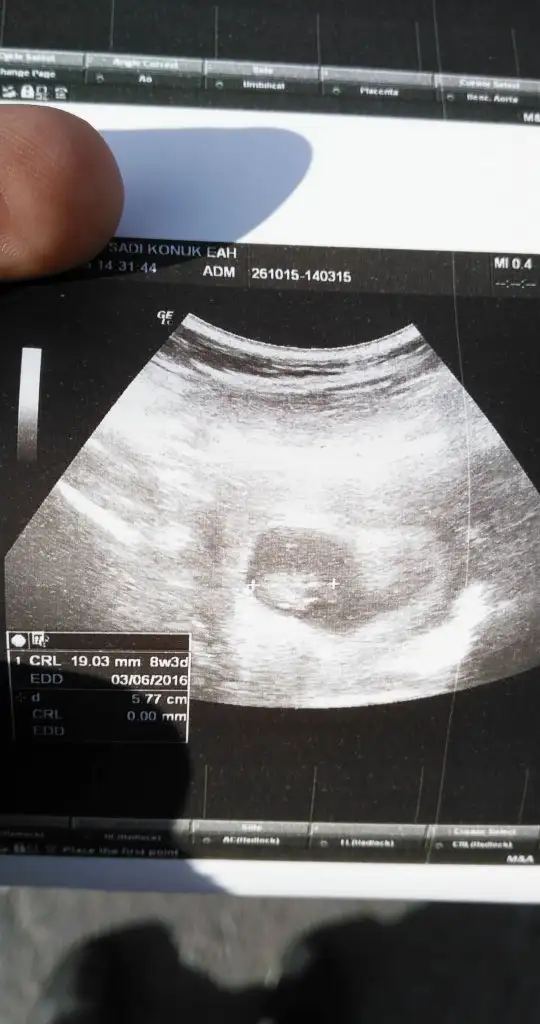

Bende anlamadım seninkini canım. Sanki büyük yuvarlak kafası gibi. Bana doktorum gösterdi tek tek ayaklarını kollarını minicik ayakları kolları vardı :) evdede izledim bol bol :)bir dahaki gittiğimizde çok büyümüş olacaklar zaten inşallah daha iyi görürüz pıtırcıklarıGozunaydn canmm cok sevndm bende dun gordum 2cm di senkinin arkasindym zaten ben resim koydum gordnmu neresi basi flan anlayamadm sen daha detayli farketmmissn banada solermisn bakip:)Eki Görüntüle 1669850

Merhaba herkese. Herkes iyidir umarım bir süredir bu sayfayı okumadım. Bebişler iyidir inşallah. Size güzel haberler vereyim. Bugün doktor kontrolümüz vardı. Bebişimiz çok iyimiş maşşallah 2.14 cm olmuş harekette etti çok güzeldiDoktor 8+5 haftalık uyumlu gidiyor çok güzel dedi. herşey yolunda çok şükür. 11. haftada gidicez tekrar ben bi erkenden ense kalınlığına bakayım dedim. 12-13. haftada 2 li yani zeka testi yaptıracaksın iyi çıkarsa 3 lü ye 4 lüye gerek kalmayacak, 20. haftadada ayrıntılı usg yaptırıp yolumuza devam edicez başka bişey yok dedi. Birde dvd verdi videosu var eve geldim izledim bebişimi. Her gittiğimde götürücem cd yi üstüne kaydedicek çok güzel bir hatıra annemede izlettim hemen :) Doktorum sağolsun iyi ki tanımışım bulmuşum çok güvenilir ellerdeyim ve çok sıcak kanlı aşırı ilgili. Allah sağlıkla kucağımıza almayı nasip etsin inşallah. İyi olduğunu öğrenince çok rahatlıyor insan

Peki karindanmi yoksa vajinalmi bakti cnm ben kendi doktruma bu hafta gitcem bu goruntu devlette cok kisa bi muayenedenBende anlamadım seninkini canım. Sanki büyük yuvarlak kafası gibi. Bana doktorum gösterdi tek tek ayaklarını kollarını minicik ayakları kolları vardı :) evdede izledim bol bol :)bir dahaki gittiğimizde çok büyümüş olacaklar zaten inşallah daha iyi görürüz pıtırcıkları

Ben çok zayıf olmama rağmen karından gözükmüyor doktor rahmin ters galiba o yüzden karından gözükmüyor hala dedi. Hep vajinal bakılıyor bi sonrakinde karından görünür heralde. 11. haftada gidicem 14 kasımda. Devletin cihazı iyi değildir o yüzden net değildir canım.Peki karindanmi yoksa vajinalmi bakti cnm ben kendi doktruma bu hafta gitcem bu goruntu devlette cok kisa bi muayeneden